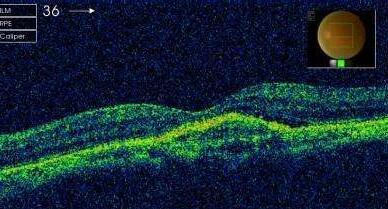

中渗